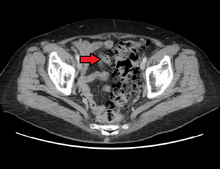

- Contrast CT is the investigation of choice in acute episodes of diverticulitis and where complications exist.